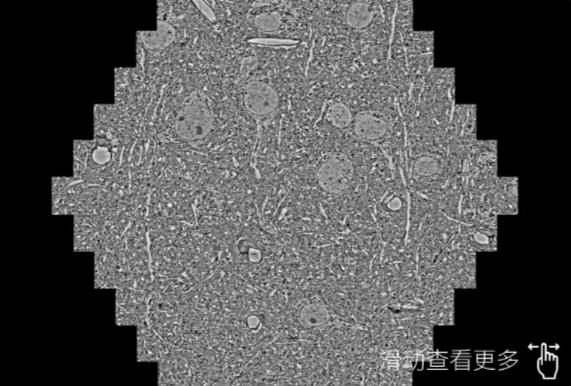

鼠脑切片。左图使用铁岭蔡司铁岭扫描电镜MultiSEM706对165μmx143pm面积区域成像,耗时仅需1.5秒。右图为鼠脑切片中30μm区域放大效果。样品由芝加哥大学B.Kasthuri提供。